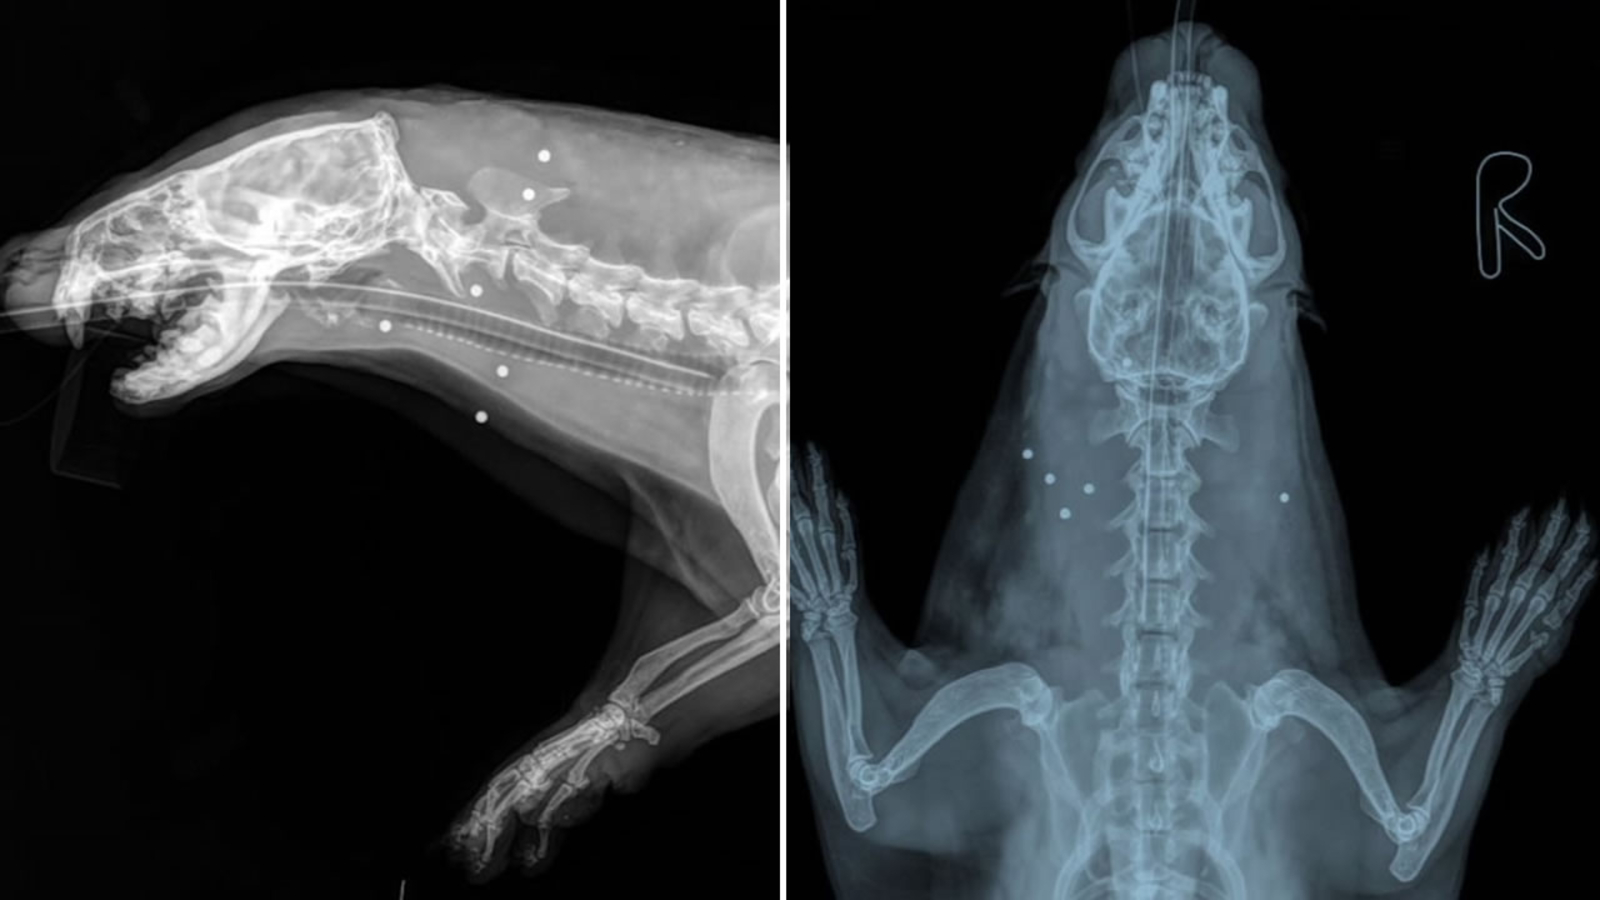

But that's apparently what happened to the male river otter found in Walnut Creek near the Shadelands Business park on Sunday. X-rays showed a half dozen bb's or possibly shotgun shot riddling its body. It was rushed to Lindsay Wildlife Hospital.

"He had broken teeth and something was going on in his mouth that wasn't right. His left eye was completely blind and in the wild, that's not a recipe for him to survive," said Lindsay Wildlife Hospital expert Elisabeth Nardi.